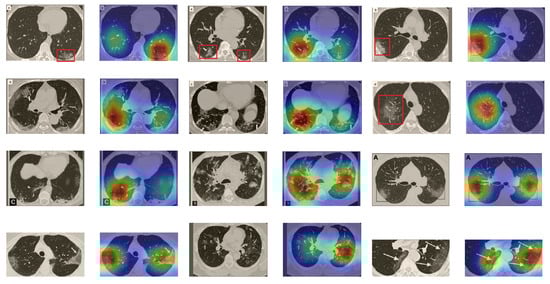

Although we trained our models using CT images where both lungs are visible in the scans, we tested them on some external CT scans where only one lung is visible. The CT scans were extracted from the paper [61] and show different CT manifestations of COVID-19 marked by red squares or white arrows. Our models were able to classify them correctly as COVID-19 cases. Intriguingly, when applying Grad-CAM we can see from Figure 17 that all regions of abnormalities are accurately localized. This also proves the potential of our models to detect COVID-19 abnormalities in CT images outside the dataset used for training.

Figure 17.

Example of annotated CT scans with different manifestations of COVID-19 taken from [61], and their corresponding localization maps. Our models were able to identify them as COVID-19 cases and accurately localize their COVID-19-associated regions.

For a comprehensive analysis of our visual explanations, we include some cases wherein the models failed to localize the exact COVID-19-associated regions. Figure 18 illustrates examples of CT scans that were correctly identified by our models as COVID-19 cases, but with which our models failed to localize the most relevant regions associated with COVID-19 as marked in some CT images. These failure behaviors can be attributed in some cases to focusing on similar findings or subtle density of manifestations found in the early days of infection. Nevertheless, in some cases the models only localized the findings in one lung and failed to highlight the disease-related regions in the other lung.

Figure 18.

CT scans and their Grad-CAM localization maps showing cases in which the model failed to localize the most relevant COVID-19 regions.